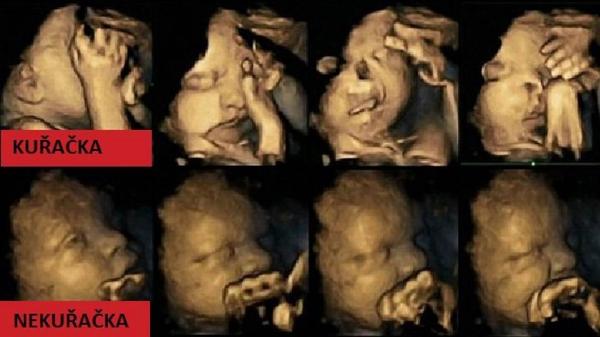

@jitulinkaaa tohle jsou ultrazvuky miminek, a rozdíl mezi miminkem nekuřačky, a kuřačky po tom co si zakouřila jen 1 cigaretu je markantní... !! miminko se dusí !! ...

@bassetlady můj lékař má prakticky to samé v čekárně... takové to obrázky + popisek všeho co se pak s miminkem děje... včetně toho že se mimininko dusí !